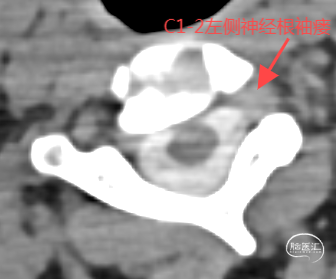

经CT脊髓造影发现瘘口,如上图。